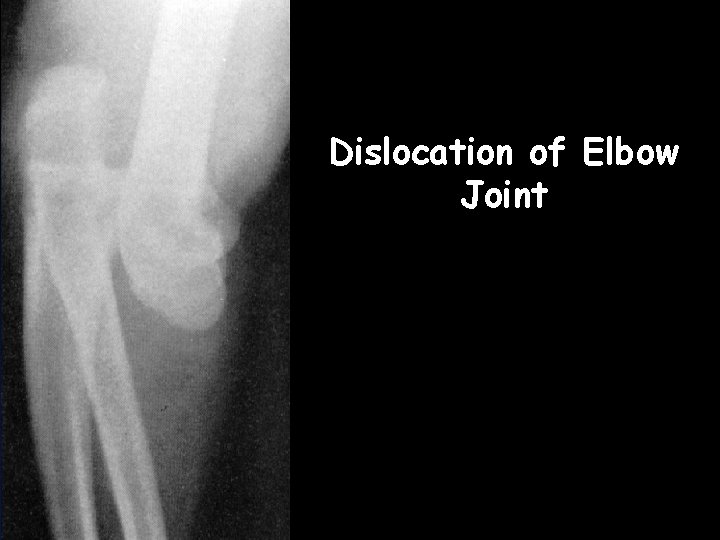

http: //www. vh. org/adult/provider/radiology/icmrad/skeletal/01 Trauma. html humerus ra s u i d a n l u Dislocation of elbow

Dislocation of Elbow Joint